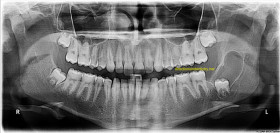

Remoção de cistos e tumores da região bucal e maxilofacial. Um diferencial da Farret Odontologia Personalizada é o uso de Laserterapia em conjunto com a cirurgia para remoção das lesões, o que já é comprovado cientificamente que contribui muito positivamente para a recuperação do paciente.